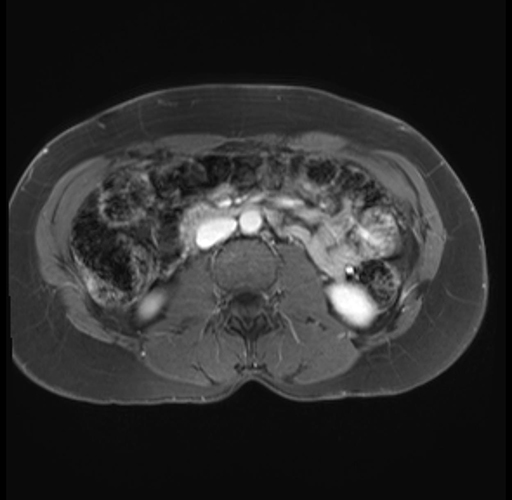

Imaging Analysis

Look through the patient's CT scan to identify any areas of concern for the necessary procedure.

Based on your CT findings, which issue(s) are present and would give reason for "planned slowing down moment(s)" in this case?

Considering a standard distal pancreatectomy procedure, what step(s) of the operation would you do differently in this case?